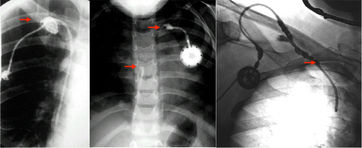

- Pinch off Syndrom bei 2%. Dabei wird der Katheter zwischen 1. Rippe und Clavicula abgeschert. Es kommt zuerst zur Extravasation bei Injektionen, dann zur Katheterfragmentation mit Embolisation in rechten Vorhof, rechten Ventrikel oder die Lunge. Solange das Katheterfragment noch im Herzen liegt, kann es oft transfemoral mit einer Schlinge extrahiert werden. Aus der Pulmonalarterie kann es nur durch eine offene Operation mit HLM entfernt werden.